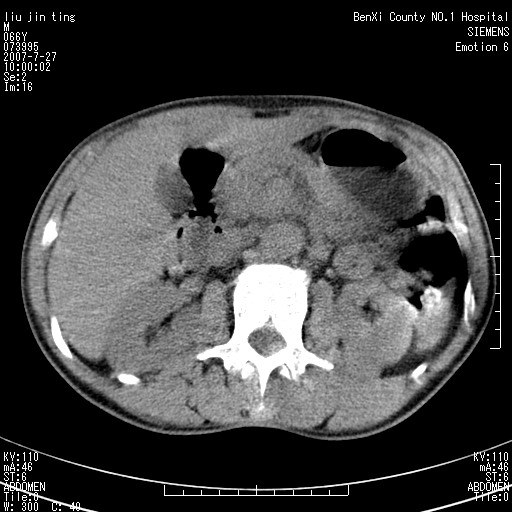

腹痛,背痛,无恶心呕吐,不黄,彩超示胰腺钩癌,ct扫描病灶平扫30-40hu,增强后动脉期40--60hu,静脉期50-68hu,真的是钩突上的么?您要试一试么?

动脉期

静脉期

沿着肠系膜上动脉呈匍匐性生长的软组织肿块,形态不规则,包绕肠系膜上动脉,呈明显强化,考虑来源于肠系膜的恶性肿瘤

沿着肠系膜上动脉呈匍匐性生长的软组织肿块,形态不规则,包绕肠系膜上动脉,呈轻-中度强化,考虑来源于肠系膜的恶性肿瘤。

钩突是正常的,只见腹膜后淋巴结的肿大,考虑淋巴瘤或转移可能。